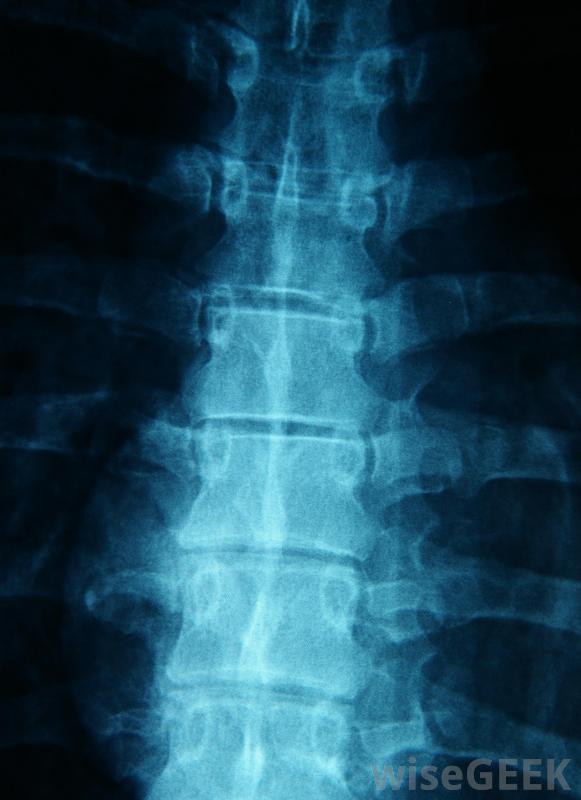

椎板间硬膜外注射是一种将类固醇输送到脊神经根部的药物。这类硬膜外注射有三种不同的类型:颈段硬膜外注射、腰段硬膜外注射和胸段硬膜外腰段注射。注入脊神经根的类固醇有助于战斗与背部、腿部、手臂和肩部相关的炎症...

腰麻硬膜外类固醇注射最常用于坐骨神经疼痛患者椎体间硬膜外注射通常用于治疗脊柱三个部位之一的炎症。在颈段硬膜外注射中,类固醇可以减轻颈、肩和臂的疼痛腰段硬膜外注射会影响下背部、臀部和臀部的疼痛,以及腿部的不适。对于胸段硬膜外麻醉,这种药物可以抑制上背部、肋骨的炎症,在某些情况下,腹部。大约50%的患者报告在接受层间硬膜外注射后,患处疼痛明显减轻。

层间硬膜外注射可用于治疗下腰痛。